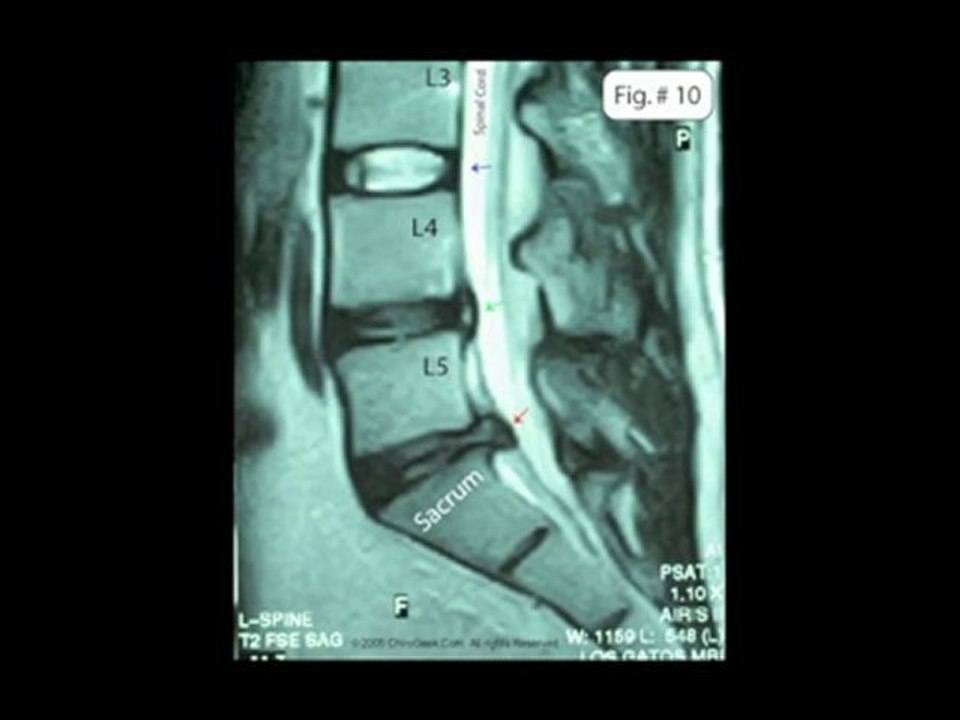

Elgin Pain Relief Chiropractor - Spinal Stenosis Treatment

http://painreliefelgin.com/ Physical therapy and chiropractic treatments like spinal decompression can provide relief from spinal stenosis. Elgin, IL chiropractors offer these treatments for spinal stenosis. Call 847-697-3472